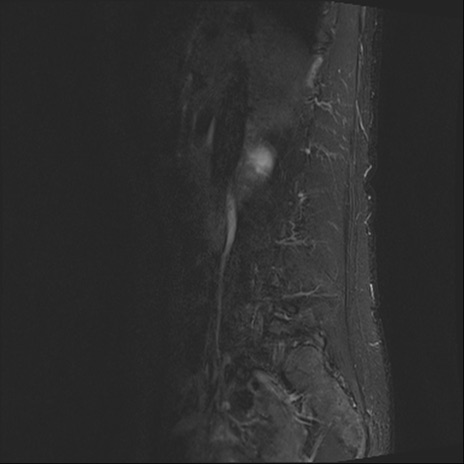

【整形】TIPS症例4 腰椎MRI STIR(矢状断像)

腰椎MRI

横断像と矢状断像